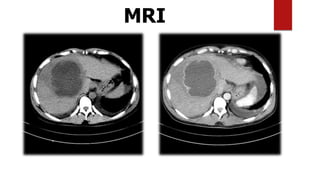

4. MRI

MRI